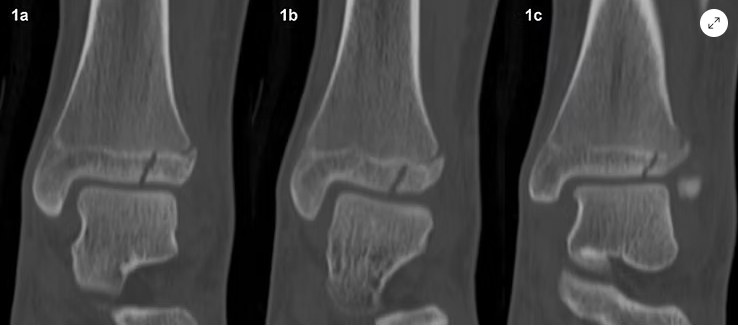

• Nota: A Tomografia Computadorizada (TC) é padrão-ouro para fraturas articulares (platô tibial, pilão tibial) e do esqueleto axial.

Reconstrução tomográfica do tornozelo com a técnica MPR no plano coronal (de anterior para posterior). Fonte: https://www.mskrad.com.br/post/fratura-de-tillaux-juvenil

Reconstrução tomográfica da tíbia distal com a técnica MPR no plano transversal. Fonte: https://www.mskrad.com.br/post/fratura-de-tillaux-juvenil